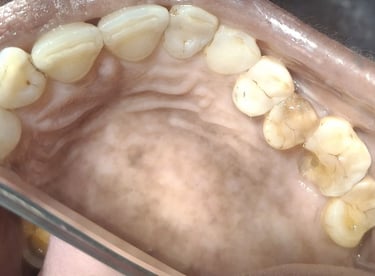

Clinical pictures of teeth requiring RCT

All images are of real cases of teeth where Root canal treatment was performed to remove infection and preserve the natural tooth restoring normal chewing and function of teeth.